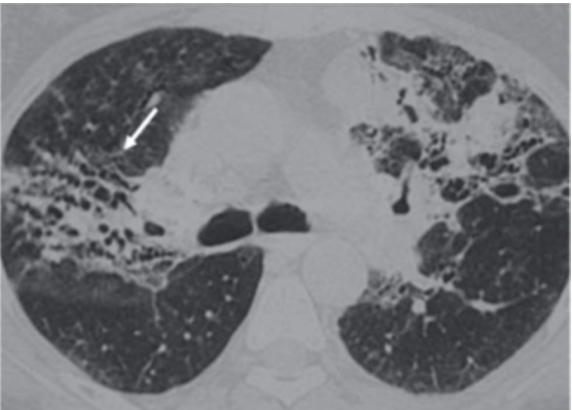

- Padrão Radiológico (OIT):

- Opacidades irregulares (lineares/reticulares) em bases pulmonares (predomínio inferior).

- Placas Pleurais: Marcador de exposição (patognomônico de exposição, mas não necessariamente de asbestose doença).

- TC de Alta Resolução: Espessamento septal interlobular, linhas subpleurais curvilíneas, bandas parenquimatosas e faveolamento (honeycombing) em casos avançados.